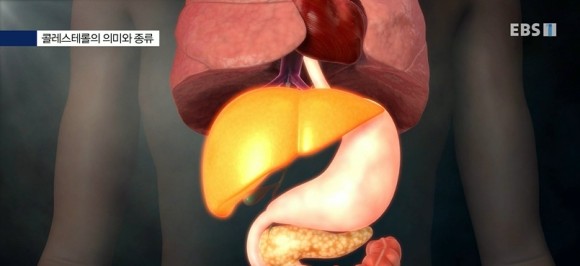

담석은 왜 생기는 것일까.간에서 생성되거나 음식을 통해 흡수된 콜레스테롤은 혈관을 타고 우리 몸 전체를 이동합니다. 이때 쓰고 남은 콜레스테롤은 간으로 돌아가 담즙으로 배출되기도 하지만 담즙에 콜레스테롤이 남아 있으면 구슬 형태로 모이게 됩니다. 이것을 콜레스테롤 담석이라고 합니다. 이 돌은 소화를 방해하고 염증이 생기기 때문에 제거해야 합니다. 그대로 두면 반복적으로 담낭염이나 췌장염을 일으키고 악화되면 담낭암으로도 발전할 수 있습니다.

간에서 과도하게 콜레스테롤이 만들어지면 그것을 처리하는 담즙의 처리량도 늘어나고 콜레스테롤이 덩어리가 되어 담석이 만들어지는 것입니다.콜레스테롤의 의미와 종류! 콜레스테롤은 반드시 나쁜 지방성분은 아닙니다. 우리 몸의 중요한 부분을 담당하여 몸을 먹이는 에너지이며 세포와 장기의 표면을 구성하는 지방 성분이기도 합니다.호르몬(성호르몬이나 스테로이드호르몬 등)을 만드는 재료이기도 합니다.

콜레스테롤의 70%는 간장에 의해 만들어집니다.콜레스테롤의 30%는 먹고 얻고 나머지는 간에서 만들어집니다. 만들어진 콜레스테롤은 지방 알갱이에 실려 혈액을 풍깁니다.